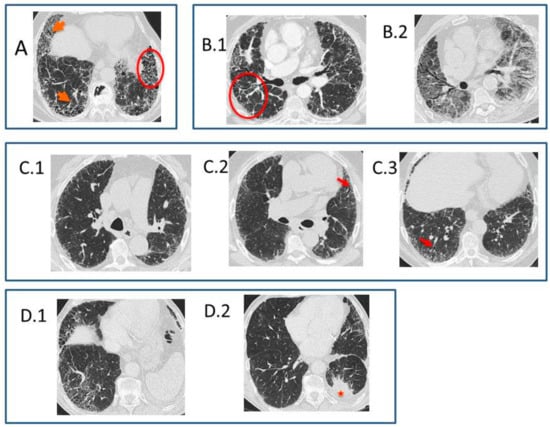

- Typical UIP CT pattern: Reticular opacities and honeycombing, with peripheral traction bronchiectasis and subpleural and basal-predominant distribution. Furthermore, there must be no other findings suggesting an alternative diagnosis (see below, Figure 2A). The fibrosis distribution can be asymmetric. This corresponds to the 2011 UIP pattern guidelines. To make an IPF diagnosis, a lung biopsy is not required in the correct clinical context and in the absence of a known cause of pulmonary fibrosis.

- Probable UIP CT pattern: Replaces the possible UIP pattern in the 2011 guidelines. It includes the same findings as the UIP pattern, although without honeycombing. A lung biopsy is not required in the correct clinical context and in the absence of a known cause of pulmonary fibrosis.

- CT pattern indeterminate for UIP: Appears when the fibrosis presents a variable or diffuse distribution or when there are inconspicuous findings suggesting a non-UIP pattern (Figure 2B). A lung biopsy is required to diagnose IPF in these patients.

- CT features most consistent with a non-IPF diagnosis: Appears when the pulmonary fibrosis is predominant in the upper or middle areas, it is peribronchovascular, it respects the subpleural area, or in any of the following features: predominant consolidation, extensive ground glass opacity without acute exacerbation, extensive mosaic pattern with air trapping on expiration, and nodules or cysts other than in a honeycomb formation. For example, fibrosis with peribronchovascular distribution predominantly in the upper areas, ground glass opacity, and air trapping in non-fibrotic areas, all suggest fibrotic hypersensitivity pneumonitis.